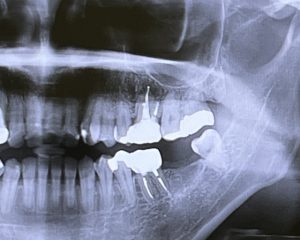

歯がある状態では、噛む刺激が顎の骨に伝わり、新しい骨を作る細胞(新しい骨を作る細胞)が働き続けています。しかし、歯を失った部分では刺激が伝わらなくなり、骨を壊す働きをする細胞の作用が優位になります。その結果、顎の骨が徐々に痩せていき、将来的に治療の選択肢が限られることもあります。

一方で、ブリッジは約90%、部分入れ歯は20〜30%、総入れ歯では約10%程度とされており、噛む力には差があると報告されています。インプラントは、顎の骨に人工歯根を埋め込み、その上に人工歯を装着する治療法です。

骨としっかり結合するため、自分の歯に近い感覚で噛むことができるのが特長です。しっかり噛めるようになることで、食事の幅が広がり、栄養バランスの整った食生活につながりやすくなります。